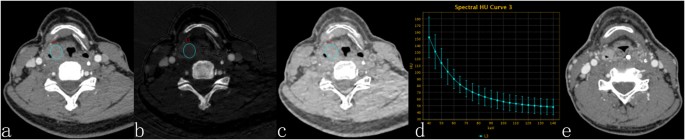

The results of the statistical analysis of the quantitative GSI parameters indicated that the sIC, λHU, and Zeff of the CR group were significantly lower than that of the NCR group, while there was no significant difference in the sWC between the two groups (Table 2). The mean sIC (P < 0.00), λHU (P < 0.00), and Zeff (P < 0.02) for the CR group were (20.51 ± 5.092 [standard deviation]) × 10−2, 1.96 ± 0.52 and 8.51 ± 0.20 VS (30.41 ± 9.61) × 10−2, 2.72 ± 0.64, 8.71 ± 0.29 for the NCR group. In addition, the mean sWC (P > 0.05) for the CR group was (1005.59 ± 6.67) × 10−3 VS (1003.98 ± 11.41) × 10−3 for the NCR group (Table 2, Figs 1 and 2).

44Y, M, hypopharyngeal squamous cell carcinoma. Contrast-enhanced GSI images before RT (a,b,c) and three months after therapy. (a) The 70-keV monochromatic image shows right pyriform sinus cancer. (b) The iodine-based material-decomposition image shows that the IC-L of ROI is 17.27·100 μg/cm3 (sIC = 0.29). (c) The water-based material-decomposition image shows that the WC-L of ROI is 1038.57 mg/cm3 (sWC = 1.01). (d) Spectral HU curve of ROI; λHU was 2.45. (e) The 70-keV monochromatic image shows the residual tumour in the right pyriform sinus, and the response assessment is NCR.